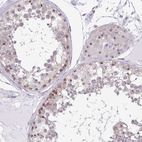

Immunohistochemical staining of human colon, kidney, liver and testis using Anti-RSL24D1 antibody HPA062724 (A) shows similar protein distribution across tissues to independent antibody HPA063392 (B).